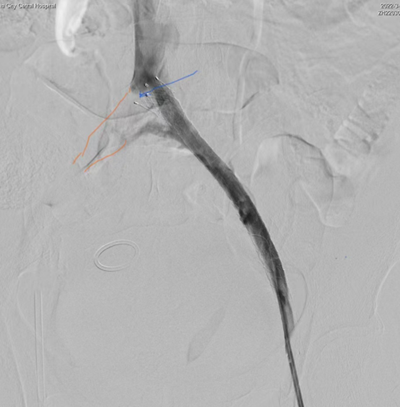

球囊扩张置入支架后左髂总造影图像。图像所示为支架头端超出左髂总静脉约1cm,距离右壁有约0.5cm距离,支架位置很好;侧支血流消失,血流通畅。